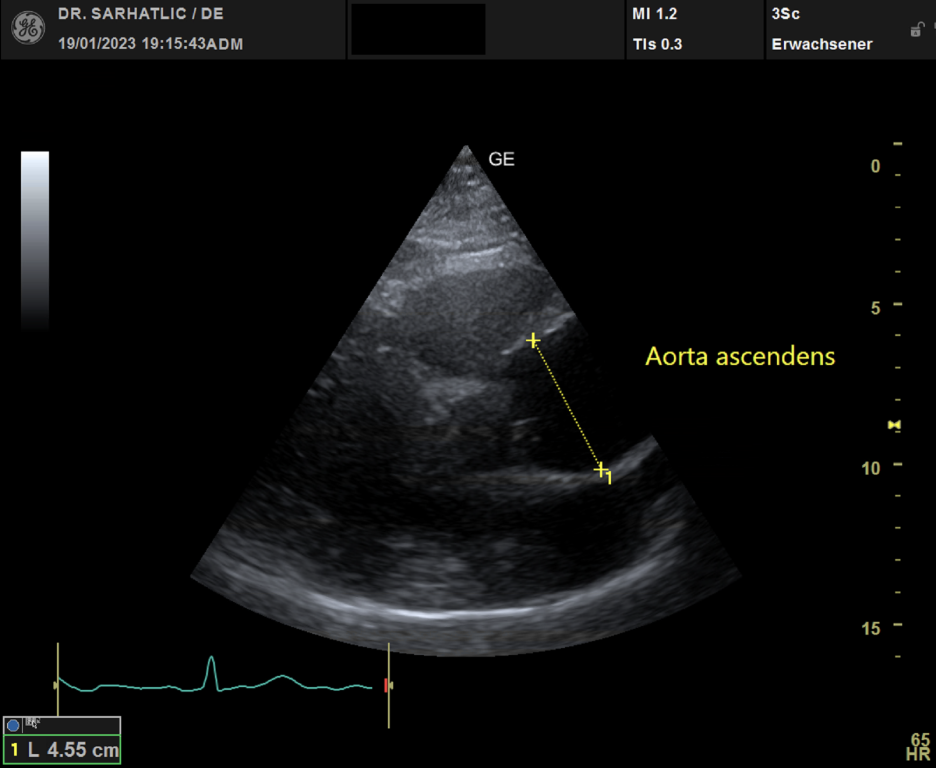

- Ultraschall des Herzens (Echokardiografie)